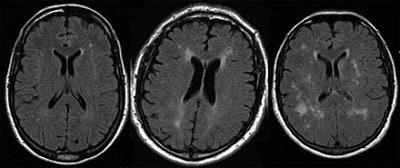

On T2-weighted and T2-weighted FLAIR MR studies, readers should look for hyperintense, asymmetric, deep, and widespread white-matter nodules. If the patient is undergoing treatment, these white abnormalities usually remain unchanged, but may worsen if the person is over age 40, the researchers stated. After therapy, the T1-weighted hypersignal of the deep gray-matter nuclei may disappear, they added.

![]() |

| A 52-year-old woman with periventricular hyperintense nodules on FLAIR imaging (1.5-tesla system; TR/TE, 9,000/146; inversion time, 2,250 msec; slice thickness, 5 mm). Nodular pattern, although nonspecific, should suggest disease in nonhypertensive patient and is related to cerebral vasculopathy involving long perforating arteries. Lidove O, Klein K, Lelièvre J, Lavallée P, Serfaty J, Dupuis E, Papo T, Laissy J. "Imaging Features of Fabry Disease" (AJR 2006; 186:1184-1191). |